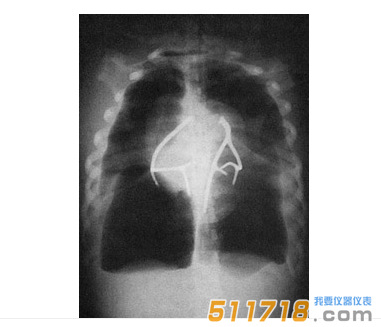

美国CIRS 602三维躯干模体